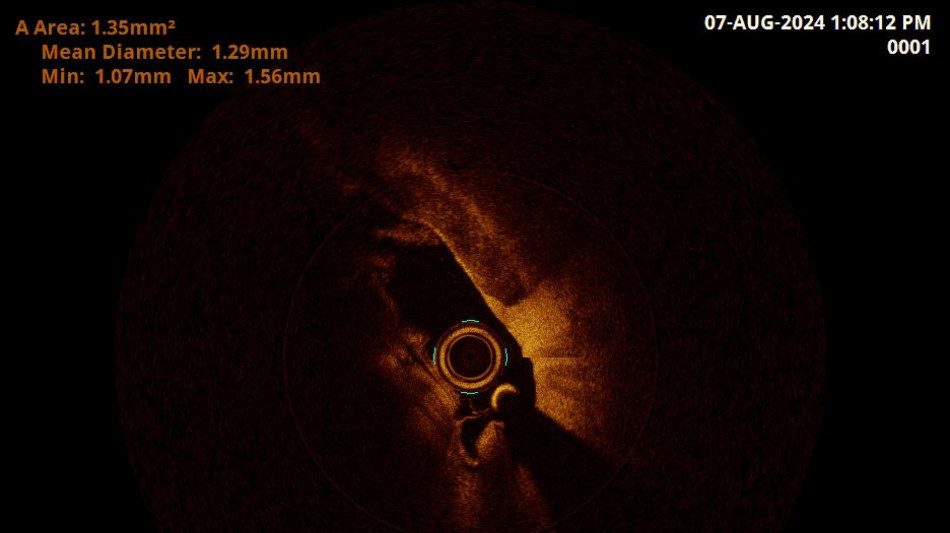

Bombay Durpun - Ospedale Grosseto vede arteria vertebrale in 3D con nuovo metodo